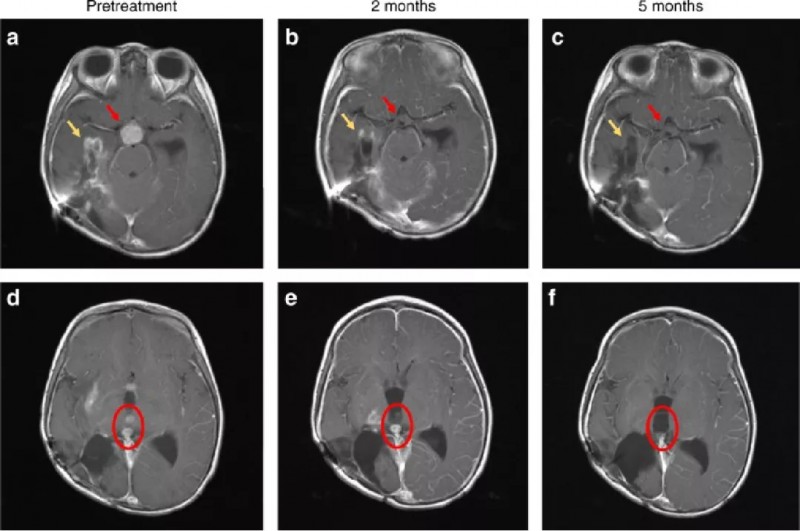

一个3岁的女孩,她在5个月大时被诊断出患有高级神经胶质瘤,在接受了手术和放化疗后,病情持续恶化,临床医生说已经没有更好的治疗办法。但是她的父母不肯放弃,用她的手术组织切片做了全基因组测序,结果显示存在ETV6-NTRK3融合,幸运的是,她入组了larotrectinib(拉罗替尼)的临床试验。仅4周后,她的嗜睡,头痛或呕吐的情况明显好转,饮食良好,说话清晰。6周后,她能够独立行走,可以正常交流,并且精力充沛。到第8周时,她跑步,跳舞并继续学习。下面的CT检查证实了她脑部的病灶已接近完全缓解!

红色箭头:脑部肿瘤治疗2个月后消退,并在5个月后持续缓解;

黄色箭头:2个月时明显改善,5个月时接近完全缓解;

红色圆圈:脑室内病变在2个月后好转,并在5个月后完全消退。